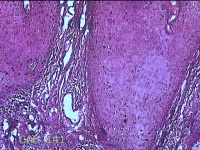

头部肿物

性别

男

年龄

21岁

临床诊断

头皮肿物

一般病史

发现头部结节10余年,无明显疼痛及不适。

标本名称

头部结节

大体所见

灰白暗红色带皮肤样结节1.5x1.3x0.3cm一个,切开结节呈实性,切面灰白粉红色,质软。